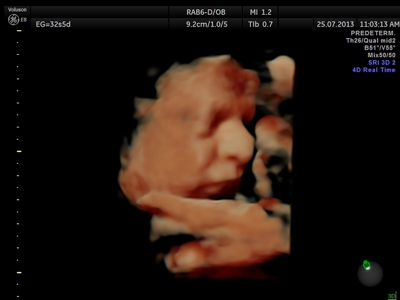

La ecografía 4D HD/5D consiste en la adquisición y presentación continúa de volúmenes. La denominación de la técnica obedece a que hay cuatro dimensiones involucradas: ancho, largo, profundidad y tiempo.

Si bien la Ecografía 4D HD/5D puede realizarse en cualquier etapa del embarazo, recomendamos realizarla entre las semanas 24 a 32 de gestación ya que se pueden observar rasgos bien definidos en el bebe.

Fotografías de ecografías 4D HD/5D

Haga click sobre las imágenes para ampliar